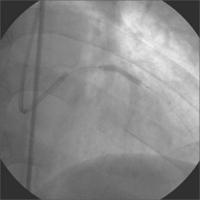

Linke Koronararterie LAO/Kaudalprojektion

Abbildung 2

Keywords: Arteria coronaria sinistraKardiologieKoronarangiographie